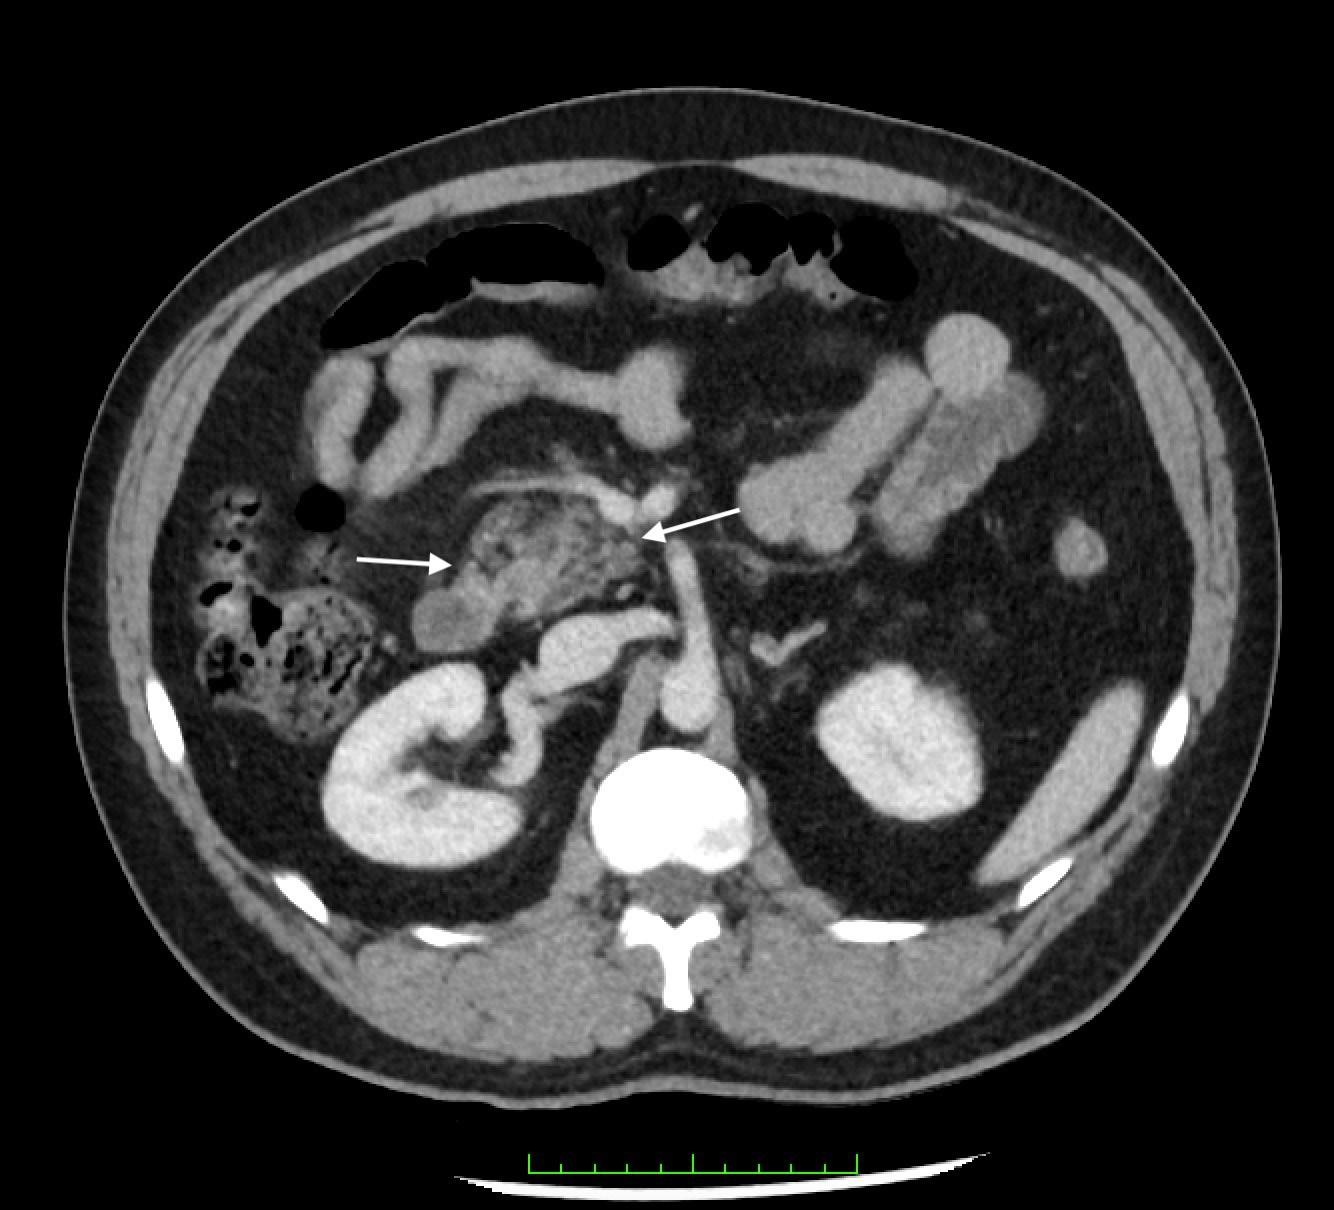

calculate bicarbonate and base excess due to a pH more than 7.70. The patient underwent an abdominal ultrasound in the ED, which suggested IHPS with an enlarged pyloric channel measuring 2.1 cm and a thickened muscle measuring 0.5 cm, again with minimal passage of fluids through the pylorus (Image 1). The surgical team was consulted for the abnormal laboratory and ultrasound findings, but due to the possibility of postoperative edema or residual abnormal external pylorus measurements, the consultant recommended further imaging to conclusively determine pyloric stenosis. The child was admitted for fluid resuscitation and electrolyte replacement. An upper GI series performed the same day confirmed the diagnosis of IHPS when there was lack of contrast passing from the stomach to the duodenum. The patient received a solution of intravenous 5%, dextrose, half normal saline, and 40 mEq potassium chloride at maintenance until electrolytes and intravascular volume

were optimized the next morning. The patient then underwent an uncomplicated open pyloromyotomy by a pediatric surgeon. The patient recovered well from the operative procedure and tolerated ad libitum oral feeds both in the hospital and at discharge. Three months following his open pyloromyotomy, the primary care clinic reported that the child had been tolerating feeds well and gaining weight adequately without any subsequent recurrence or complications of IHPS.